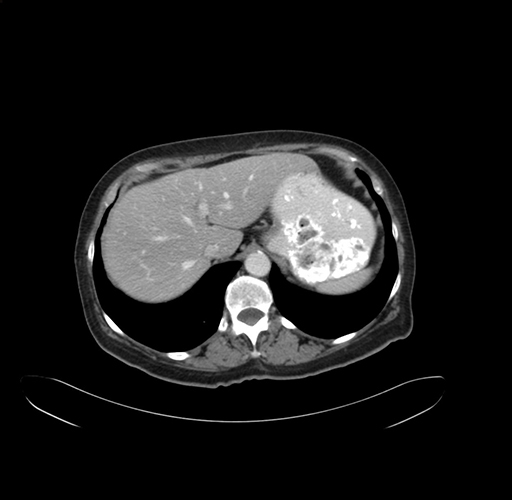

Axial Venous